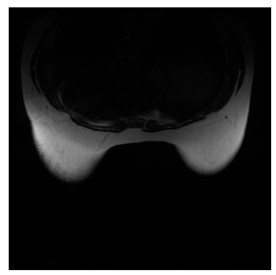

Breast-MRI-NACT-Pilot is an MRI-type image database, collecting breast medical images of 64 patients. Some samples are shown in Figure 12a.

Figure 12.

Sampled images in the tested benchmark databases: (a) Breast-MRI-NACT-Pilot (breast), (b) ACRIN-DSC-MR-Brain (brain), (c) NIH (chest), (d) Lung-PET-CT-Dx (lung), (e) Prostate-MRI (prostate), and (f) Other grayscale standard images.